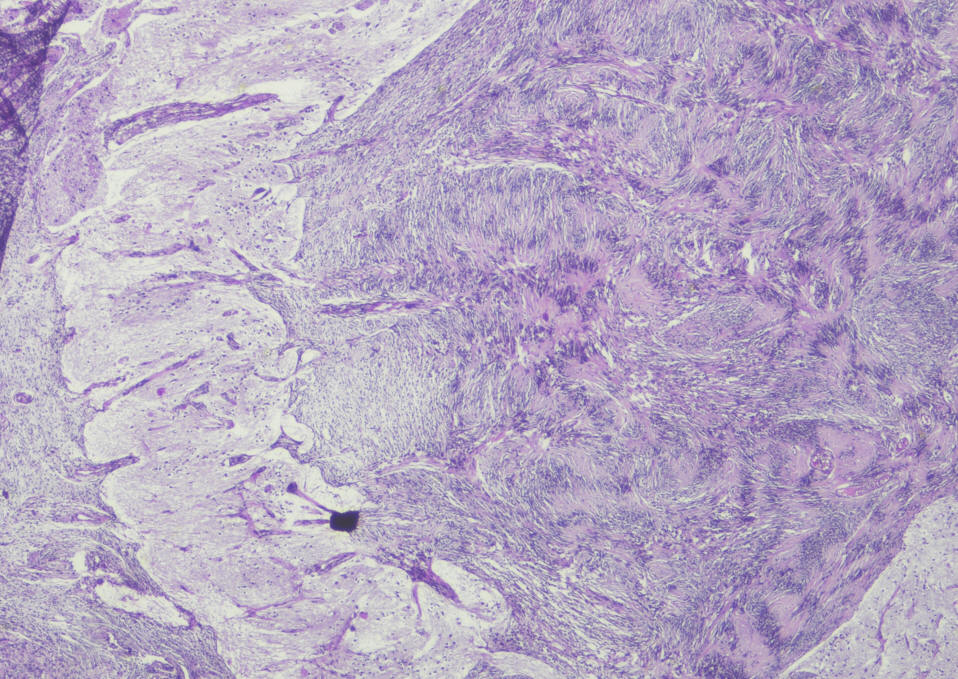

Sections show a circumscribed tumor composed of spindle cells displaying prominent nuclear palisading and Vercoy bodies. This lesion exhibits peripheral tongues extending into the brain cortical tissue. There is no evidence of mitotic activity, nuclear anaplasia or necrosis. Tumor shows heavy interstitial reticulin deposition and reacted positively to S-100 and Vimentin. Tumor did not react to GFAP and EMA. Proliferative index was estimated at 2%, but not exceed 3% in any area. There is no evidence of malignancy. Conclusion: Intracerbral schwannoma. ( Prof. Yahya F. Dajani Consultant pathologist. 29-January-2022.